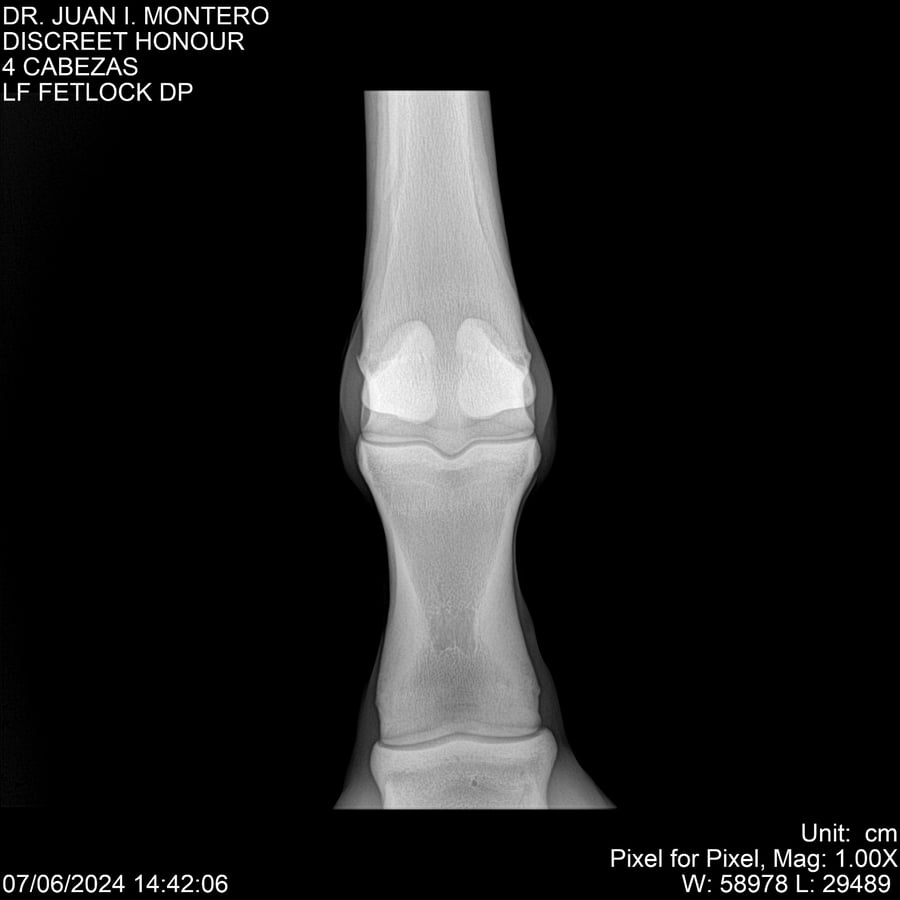

LOTE 6, DISCREET HONOUR 🔥 🔥 🔥 Lote Anterior Volver al remate Lote Siguiente Ficha Contacto Montevideo - Ficha del Lote Identificador: #281093 Categoría: Yeguarizos Montevideo - 82 Visualizaciones ClicData Contacto Empresa: Abelenda N. R., Walter Hugo Nombre*: Teléfono* : E-mail* : Mensaje Enviar Registrese gratis Este contenido Exclusivo está disponible sólo para usuarios registrados Ingresar